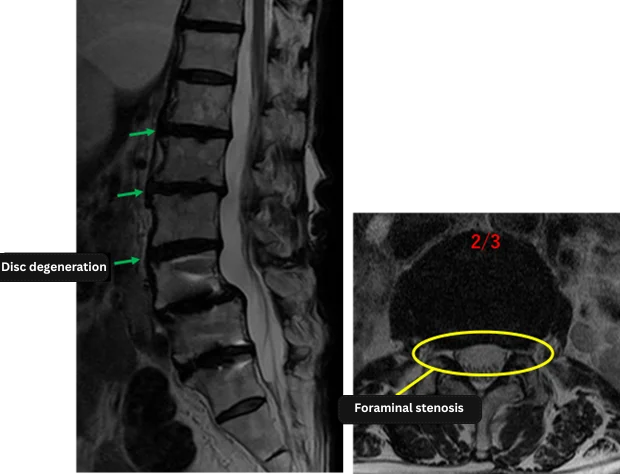

| Disc Level | Findings |

| L1/2 | Disc Degeneration |

| L2/3 | Disc Degeneration, Bulging, Left Foraminal Stenosis |

| L3/4 | Disc Degeneration |

| L4/5 | Post-operative (Fusion site) |

| L5/S | Post-operative (Fusion site) |

The above findings were also observed on the imaging.

Based on imaging, disc degeneration, bulging, and left foraminal stenosis at L1/2, L2/3, and L3/4 are considered the most likely sources of symptoms.